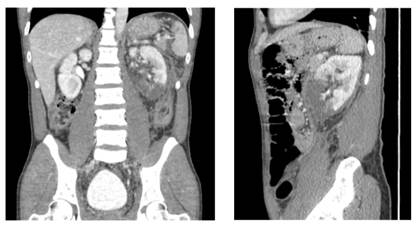

A 42-years-old male with no medical history, presented to the ER of another center with abdominal pain after falling from an e-scooter at 30km/h while riding it under alcohol influence, 3 days later the patient presented to our ER for persistence of pain. Physical examen showed pain with the abdominal palpation but without alarming findings. A CT scan was performed noticing a left kidney inferior pole hypoperfusion, a spleen laceration, and a left lung contusion (Figure 5 & 6). Classified as a AAST grade IV, the patient was hospitalized for close vigilance, kept stable during hospital admission with normal GFR and hemoglobin therefore receiving a conservative management and was sent home with no complications. The follow up CT showed resolution of the lesions.

Case 4

A 19-years-old male with no medical history, presented to the ER with abdominal pain after crashing against a light pole with an e-scooter at 60km/h while trying to avoid a car. Physical exam showed many bruises and left abdominal pain. The CT scan showed four broken right ribs, right pulmonary contusion and pneumothorax, splenic laceration, and left kidney corticomedullar laceration with lesion of the collecting system (Figure 7 & 8) which required a double J stent placement.

Axial and coronal planes. A 13mm corticomedullar laceration of the left kidney with lesion of the collecting system. Spleen laceration

Figure 7 & 8 Contrasted abdominopelvic CT scan